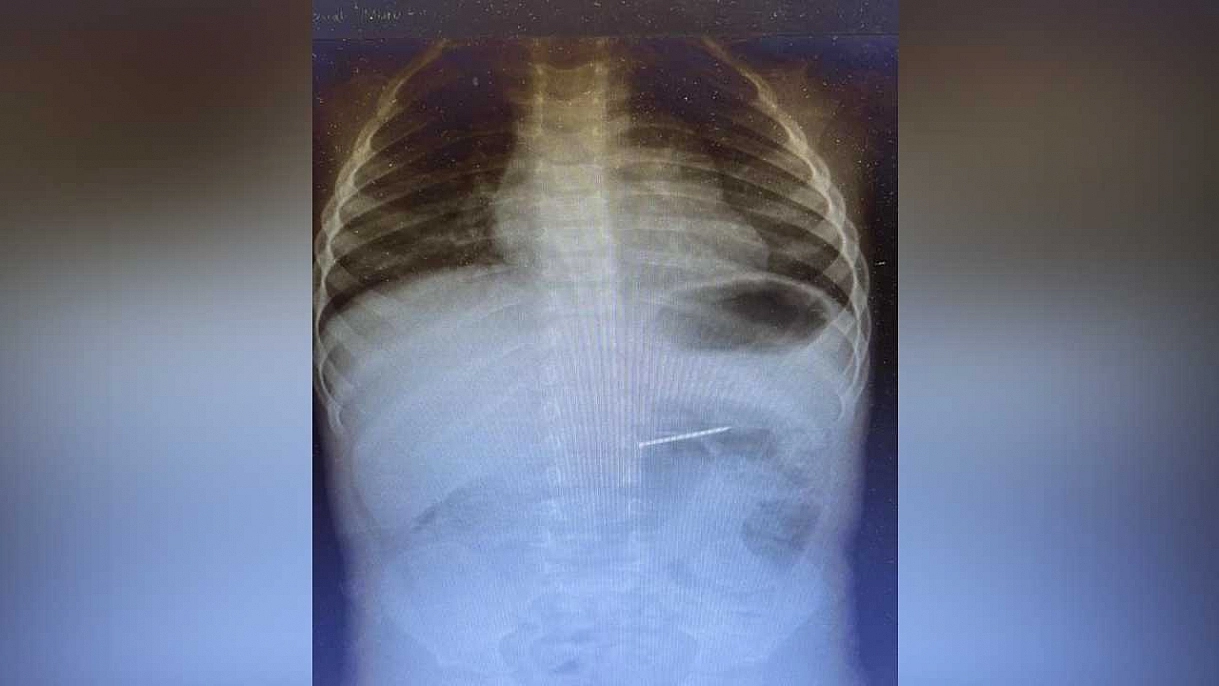

2 yaşındaki çocuğun midesinden 4 santimetrelik çivi çıktı

2 yaşındaki çocuk, yuttuğu 4 santimetrelik çivi endoskopik yöntemle başarıyla çıkarıldı. Uzmanlar, aileleri evdeki tehlikeli nesneler konusunda uyardı.

Radyolojik inceleme sonucu yaklaşık 4 santimetre uzunluğundaki çivinin midedeki konumu tespit edildi ve hemen endoskopik müdahale yapıldı. Yapılan işlemle çivi, herhangi bir komplikasyona yol açmadan başarılı şekilde çıkarıldı. Hasta, kısa süreli gözlem amacıyla serviste takip altına alındı ve sağlık durumu stabil şekilde taburcu edildi.